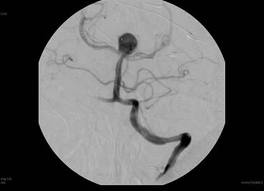

Pada bulan Desember 2012 ini, saya mendapatkan kehormatan dengan diundang untuk melakukan tindakan kateterisasi otak atau yang disebut dengan “Endovascular Neurosurgery / Neuro Intervensi” di kota Medan. Tindakan ini merupakan kekhususan keilmuan bedah saraf yang sempat saya pelajari di Jepang pada tahun 2011. Saya mendapatkan undangan dari seorang dokter spesialis bedah saraf disana, Dr. dr. Ridha Dharmajaya, SpBS, dimana beliau juga adalah senior saya selama menjalani pendidikan bedah saraf di Departemen Bedah Saraf FKUI-RSCM dulu. Sebanyak 7 pasien dapat beliau kumpulkan dan terima untuk menjalani tindakan kateterisasi otak tersebut. Sebagian besar dari pasien-pasien tersebut datang dengan keluhan kelumpuhan akibat serangan stroke yang sudah diderita beberapa hari hingga beberapa minggu sebelumnya. Keluhannya bervariatif namun sebagian besar datang dengan kelumpuhan satu sisi tangan dan kaki. Ada juga dengan keluhan sulit berbicara hingga “cadel”. Tindakan kateterisasi ini saya tujukan untuk melihat dengan jelas struktur pembuluh darah otak dan mencari pembuluh darah otak yang mengalami sumbatan tersebut.

Alhamdulillah, 7 kasus tersebut dapat diselesaikan dalam 1 hari tanpa ada halangan yang berarti, dan kita dapat menemukan lokasi-lokasi tersumbatnya pembuluh-pembuluh darah tersebut. Hampir seluruh kasus menunjukkan kelainan yang nyata yang terlihat dengan jelas sekali dari tindakan angiografi/kateterisasi yang kita lakukan. Dengan diketahui secara jelas lokasi dan jenis gangguan yang mengakibatkan hambatan aliran darah ke jaringan otak maka saya dapat memberikan rekomendasikan tindakan atau tatalaksana selanjutnya yang sebaiknya dilakukan. Pilihan memang terbuka antara tindakan operasi membuang “plaque” di dalam pembuluh darah atau tindakan pemasangan stent dengan tujuan memperlebar pembuluh darah yang menyempit atau tertutup tersebut.

Saya tetap memotivasi dan menyarankan kepada seluruh masyarakat Indonesia untuk melakukan “screening” pembuluh darah otak, khususnya bila telah memiliki faktor resiko kemungkinan sumbatan seperti adanya penyakit tekanan darah tinggi, penyakit gula, penyakit kadar kolesterol yang tinggi, penyakit jantung, obesitas dan tentunya faktor usia. Dengan tindakan “angiografi/kateterisasi otak” kita dapat memeriksa dan mengetahui pembukuh darah mana yang merupakan calon untuk mengalami sumbatan atau calon untuk pecah. Cegahlah sebelum terjadi penyumbatan atau pecahnya pembuluh darah tersebut. Cegahlah stroke dan selamatkan produktifitas anda semua.